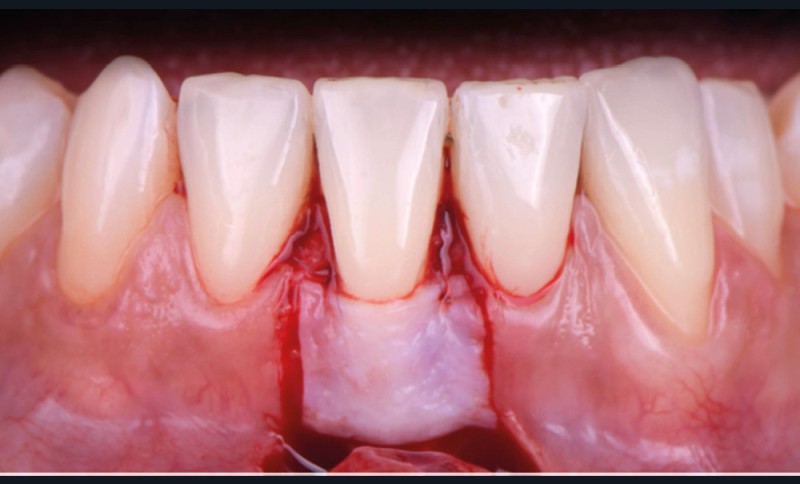

Le lambeau positionné coronairement associé à une greffe de conjonctif enfoui (fig. 1-4)

La stabilité du lambeau est primordiale dans la réussite de cette technique de recouvrement. En cas d’instabilité, même en l’absence d’erreurs techniques, l’analyse de certains facteurs liés au patient est indispensable. Afin de maintenir la stabilité du lambeau jusqu’à la dépose des points, le praticien doit veiller à l’adéquation du contrôle de plaque effectué par le patient, à l’absence de mastication impliquant la zone d’intervention, à la prévention de tout traumatisme ou de modifications des conditions locales par le patient.

Selon le Dr Sylvie Pereira, contrairement au maxillaire où la hauteur du lambeau déplacé coronairement est déterminée par la profondeur de la récession, à la mandibule, les incisions horizontales sont placées de manière à obtenir au moins 2 mm de tissu…